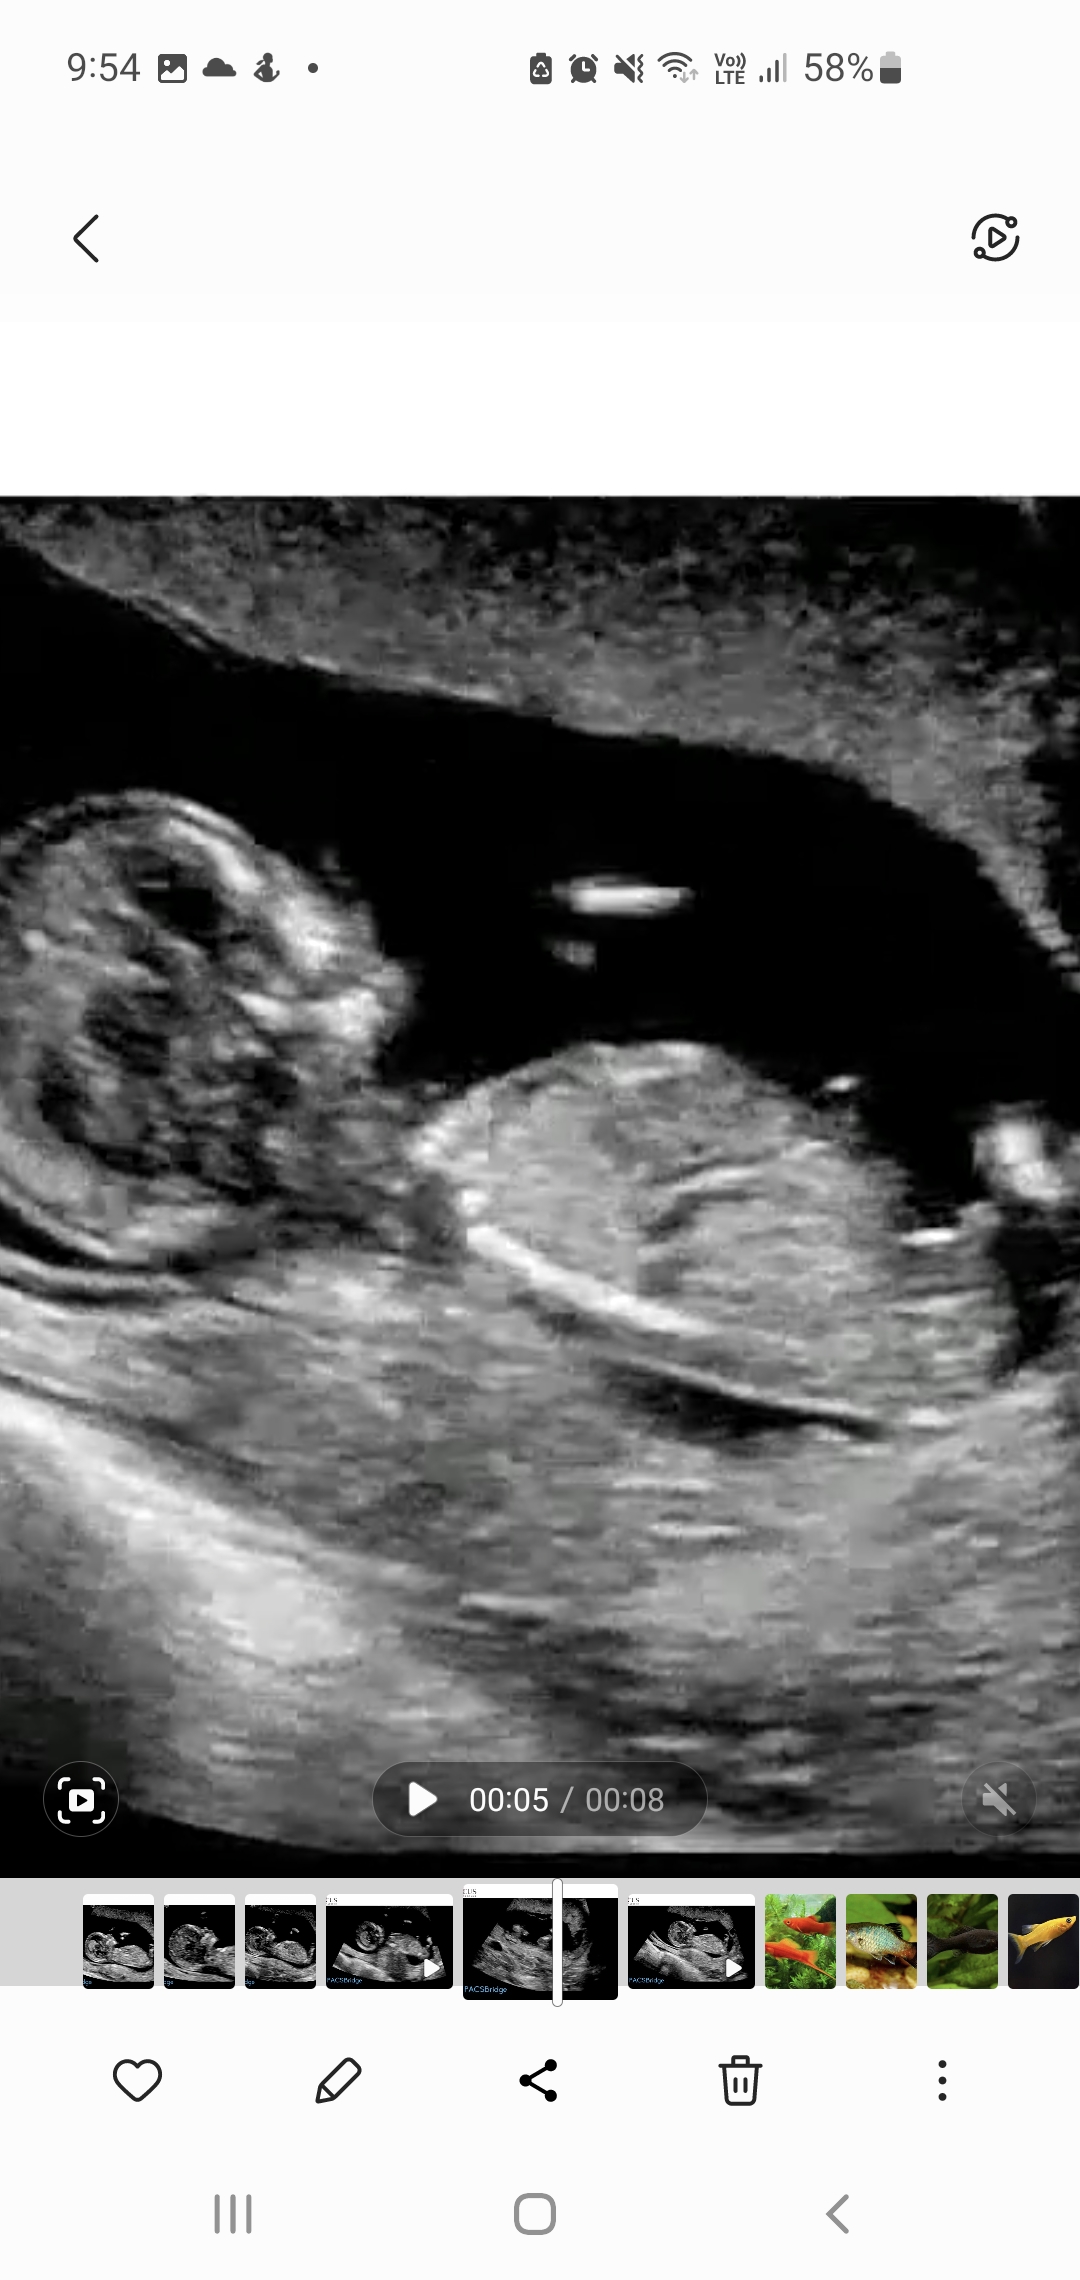

5th baby nub opinions please! 13th week

I swayed pink for a sister for my dd so I'll be honest I'm looking for hope this is a girl. So far only had boy comments elsewhere although some of the mods are 'maybe' boy, not 99%.

Atomic you've seen one of my pics in my swaying thread already but these are some more I've got from pausing the video (every micro second!). Baby was not in perfect sagittal position. I did during the scan see flashes of a long white, flat nub but she didn't capture it. She was trying to image the legs for nicer pics!

The skull/face reminds me of DDs scans but I've dreamt this bub is a boy which also happened just before I found out DS3 was a boy.

Gestation is 12+6 by OPKs & BBT, 13+5 by CRL.Attachment 43684Attachment 43685Attachment 43686Attachment 43687Attachment 43688